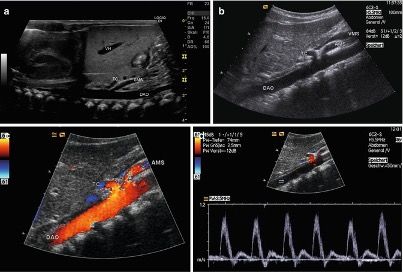

- Eco-Color-Doppler (ECD) dei tronchi sovra-aortici (TSA), ECD dell'aorta addominale e dei vasi iliaci, ECD aorto-iliaco, ECD celiaco-mesenterico, ECD degli arti inferiori arterioso o venoso, ECD degli arti superiori arterioso o venoso, ECD testicolare, ECD delle arterie temporali, ECD trans-cranico senza mdc.